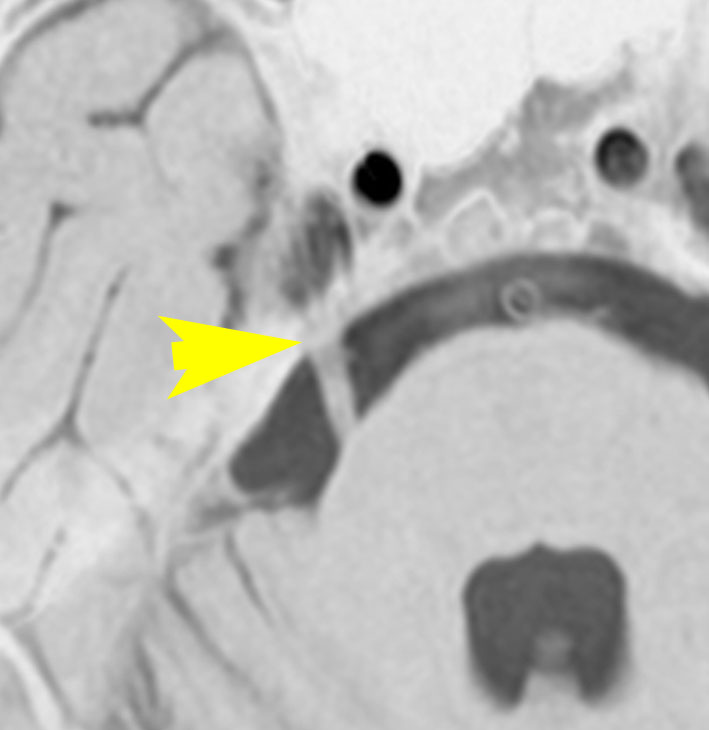

38歳の時に典型的な左三叉神経痛で発症しました。左はMRIT2,右はフレア画像です。小脳と脳幹部の間に巨大な血管がみえます。これは生まれつきの静脈の奇形 (venous anomaly)です。この血管は脳幹部と小脳のかなりの部分の血流を還流しています。出血などはみられませんが,脳幹左側の三叉神経核と神経路に血流障害があるものと推定されます。このタイプは手術で治すことができません。カルバマゼピンは有効でしたがアレルギーのために使えなくなり,ガバペンチン 1800mg/日で痛みはなんとか我慢できています。24年の間に試した他の薬は何も効きませんでした。